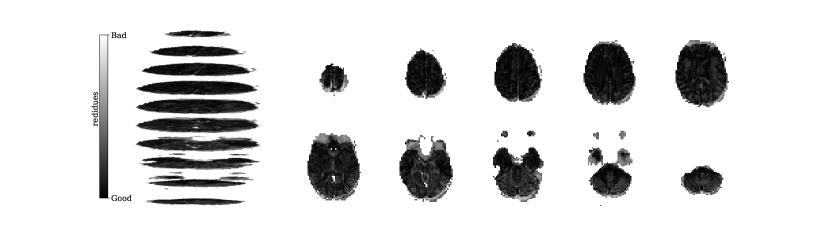

Figure 2 illustrates the distribution of residues (observed vs. estimated differences) on the fMRI volumes for the NODDI dataset. Clearly, by visual inspection, (iv) model has the darker and biggest area of shaded regions, which implies a better coverage across the brain regions and better synthesis quality. Models with topographical attention, (ii) and (iv), corresponding to Figures 2(b) and 2(d), respectively, significantly improve the synthesis, as shown by the darker and bigger areas against (i) and (iii) depicted in Figures 2(a) and 2(c), respectively. Particularly, we notice that models (i) and (iii) report difficulty in the retrieval of haemodynamical activity located in occipital and parietal lobes.

To better address which regions our baselines had more difficulty retrieving, the normalized residues were computed and are illustrated in Figure 3. Baselines – corresponding to models (i) and (ii), shown in Figures 3(a) and 3(b) respectively, which correspondingly implement a linear projection in the latent space and topographical attention –, have difficulty retrieving the prefrontal, occipital and parietal lobes, as the shade tends to a lighter grey in that region. Model (iv), shown in Figure 3(d), does not show a noticeable region with a lighter tone of grey, which implies no evident difficulty in retrieving haemodynamical activity across the different brain regions.